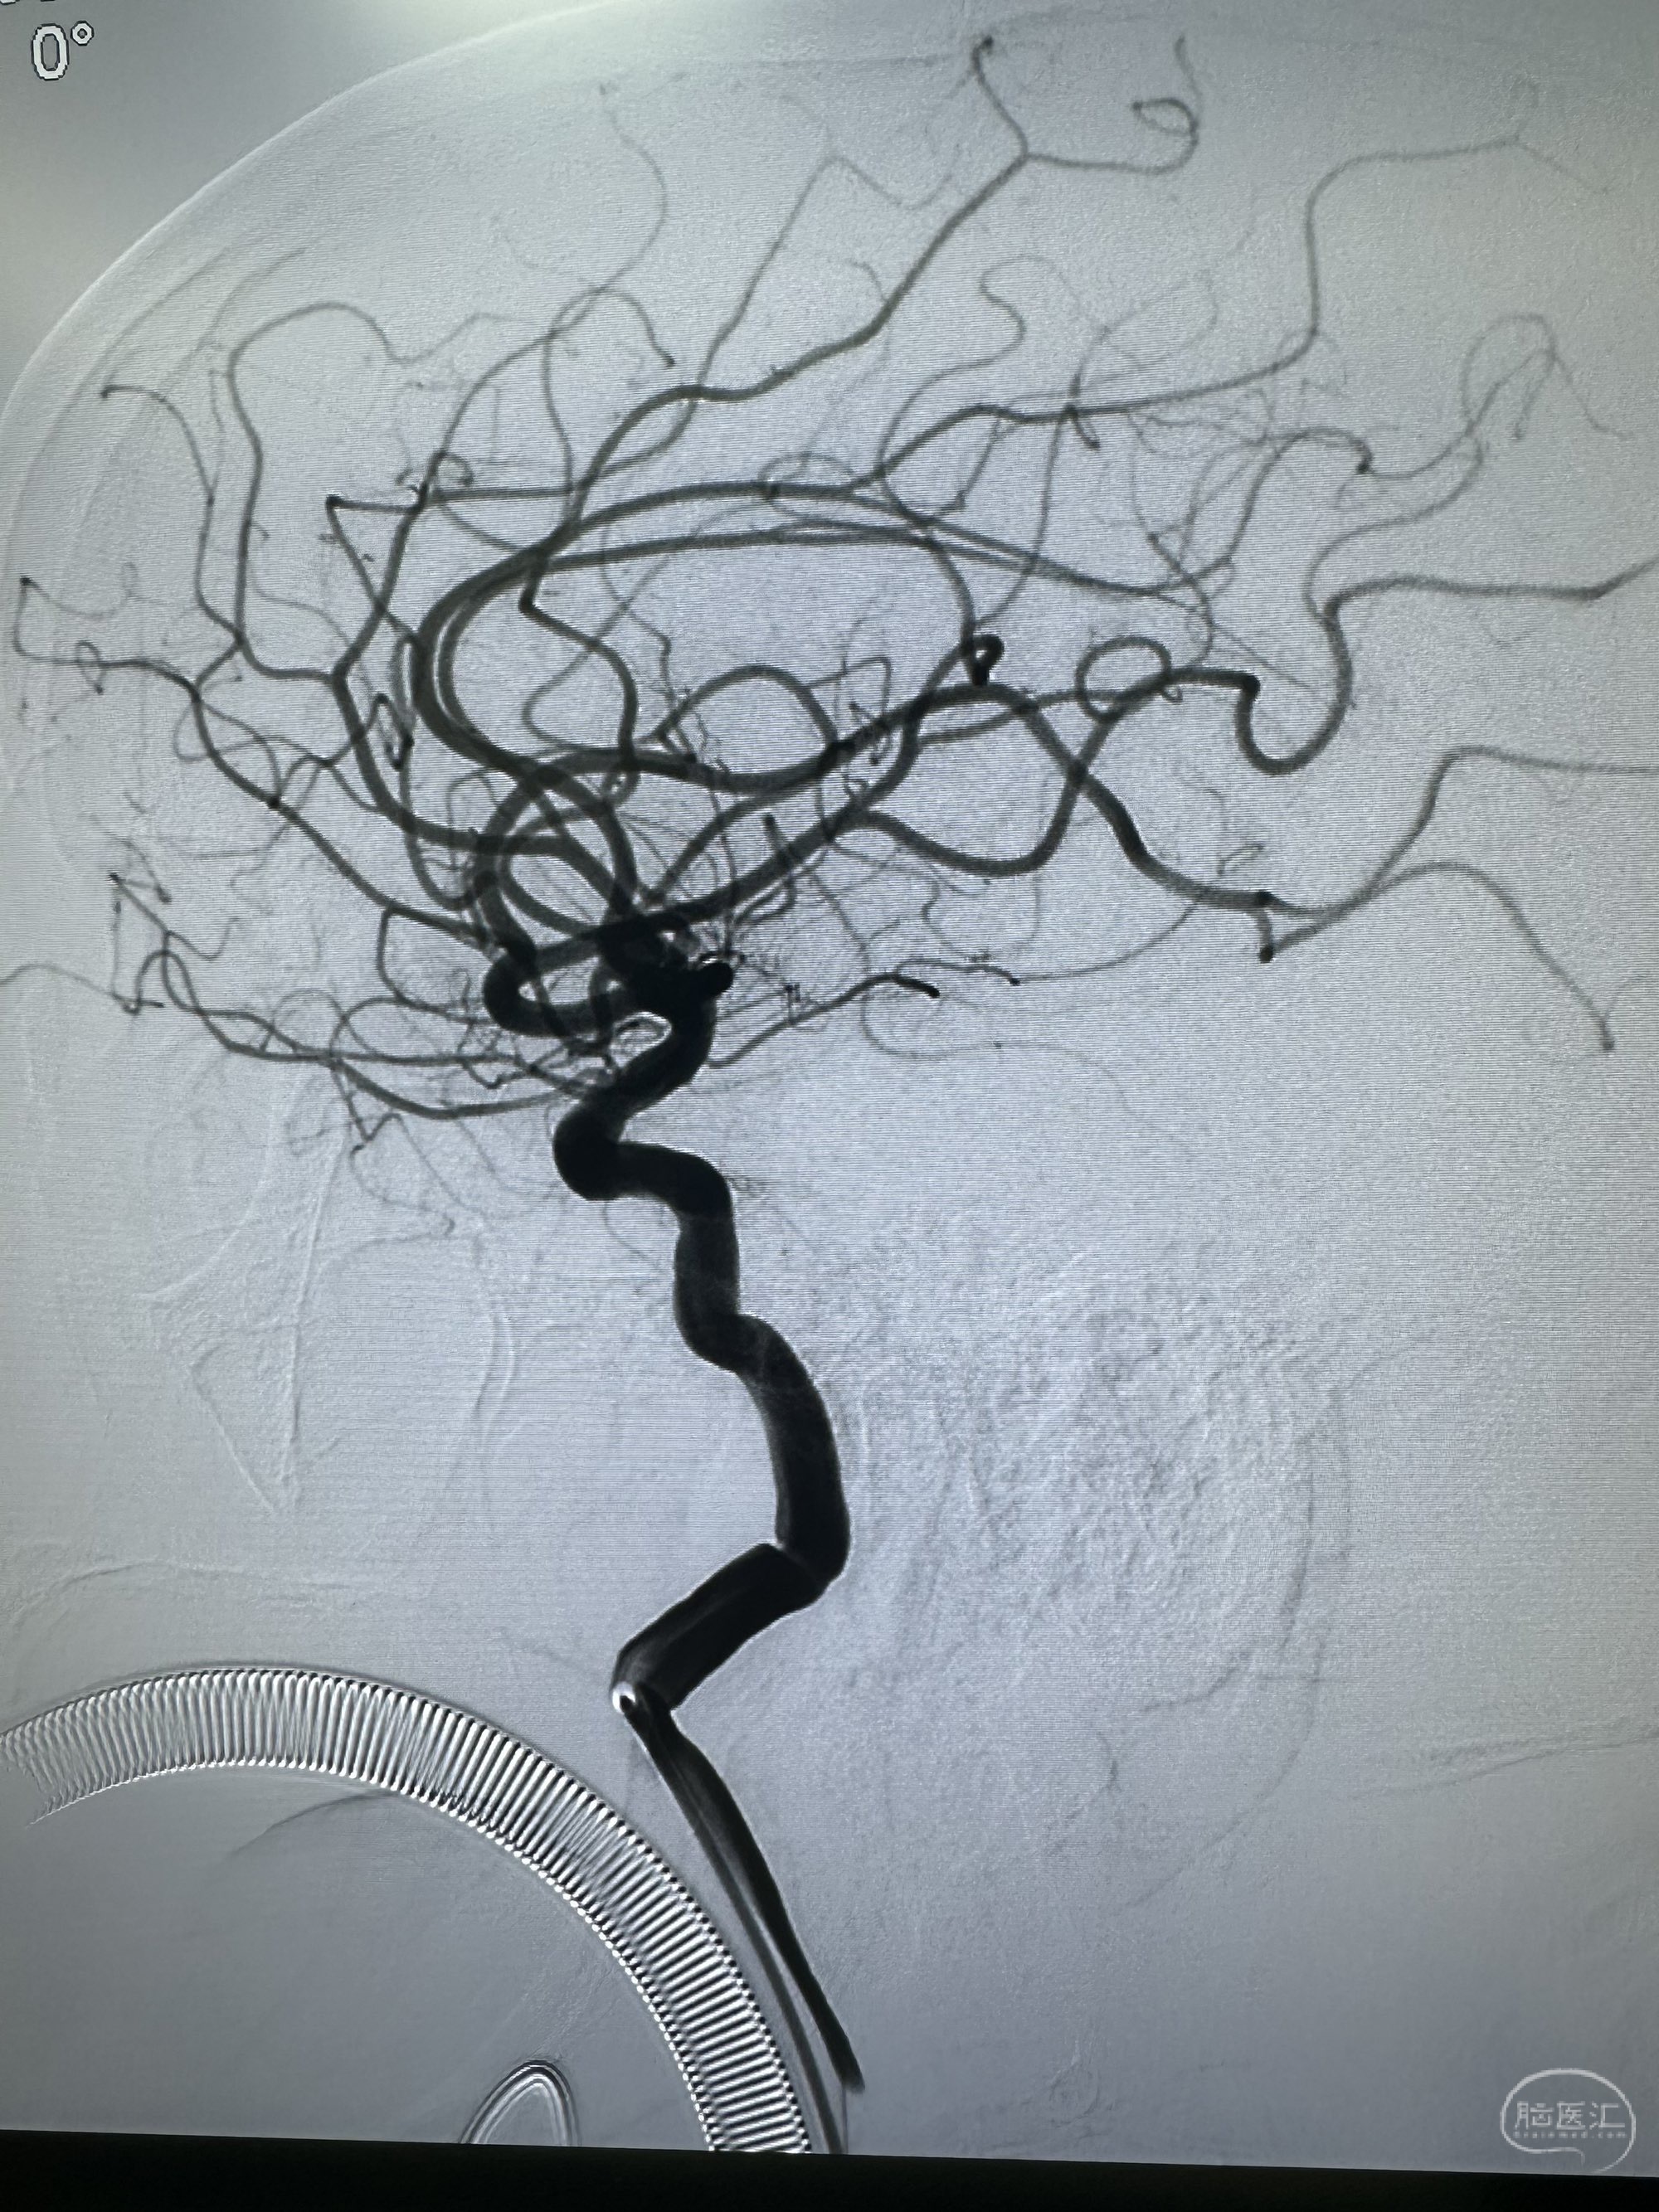

侧位